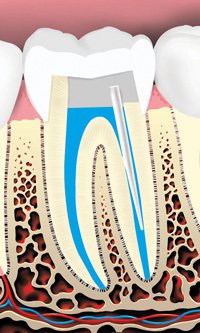

Tooth decay can cause an abscess (infection)

The decay is removed and an opening is made through the crown of the tooth into the pulp chamber.

The pulp is removed and the root canals are cleaned and shaped.

The root canals and pulp chamber are filled.

A metal or plastic rod or post may be placed in the root canal to help retain the core (filling) material, which supports the restoration (crown).

The tooth is then restored with a crown or filling.